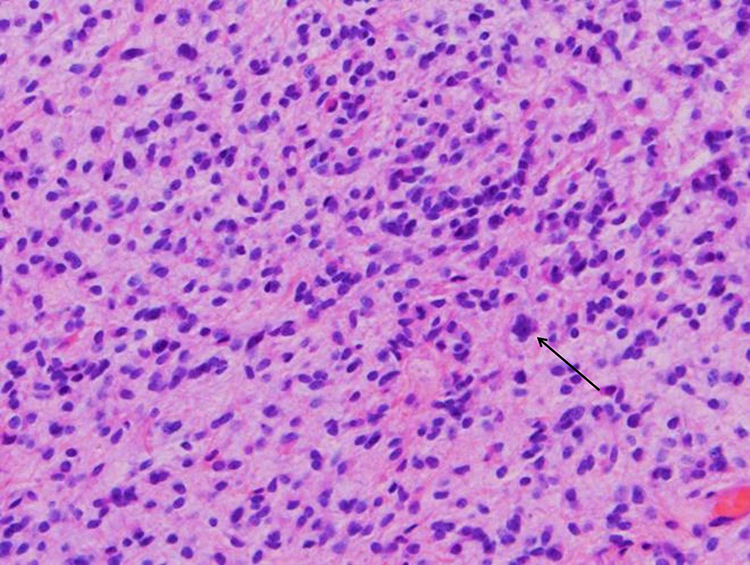

Describe the Histologic Features in Figures 2-4

The patient underwent a suboccipital craniectomy and a biopsy of the lesion. Intraoperatively, no clear distinction between normal and lesional tissue was apparent. On the permanent section (hematoxylin and eosin stain), the lesion demonstrates areas of moderate-to-high cellularity with occasional mitotic figures. The neoplastic cells are bland and monomorphic with round to oval nuclei and no prominent nucleoli (Figure 2). In some areas, the lesional cells are growing around and entrapping neuronal processes, specifically targeted by an immunostain that highlights neurofilaments, highlighted in brown in the figure (Figure 3). Neurofilaments are an intermediate type of filament that are present in the cytoplasm of neurons. Focal areas of microvascular proliferation (thickened vascular walls secondary to endothelial cell hyperplasia and hypertrophy with formation of multiple lumina), thrombosed vascular lumina, and necrosis are present (Figure 4).

Areas of moderate to high cellularity with occasional mitotic figures (black arrow). Magnification = ×40.